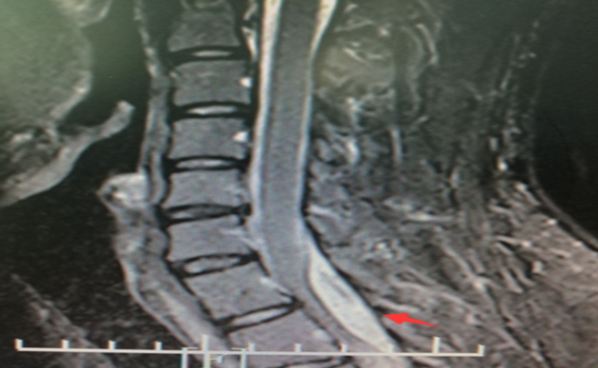

长沙市第四医院医生妙手巧拆定时炸弹

300x238 - 27KB - JPEG